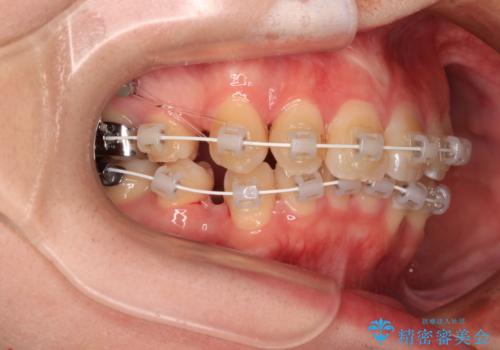

- 矯正装置

- 審美装置

口元の突出感はなかったものの、捻転や八重歯を改善するために補助装置を併用する必要がありました。

予定の2年半を越えてしまいましたが、無事にきれいな口元に仕上げることができました。